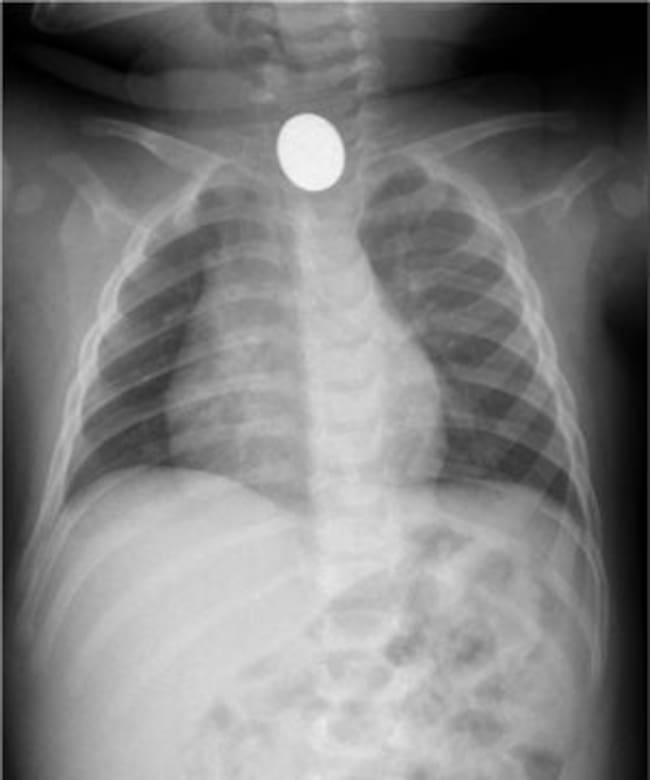

Els radiòlegs catalans comencen demà el seu congrès , dedicat a la radiologia d’urgències. Una de les situacions més habitual d’aquests especialistes és la intervenció provocada per la ingesta d’un objecte o cos estrany.

Segons informen els organitzadors del congrés, cada setmana hi ha casos d’aquest tipus en els hospitals catalans, que afecten majoritàriament a infants, però només un petit percentatge d’aquests requereix finalment hospitalització. La majoria d’ocasions els objectes deglutits són monedes.